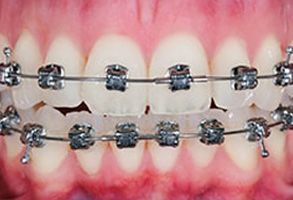

Before

Before

Before

Before

Before

Before

Before

Before

Before